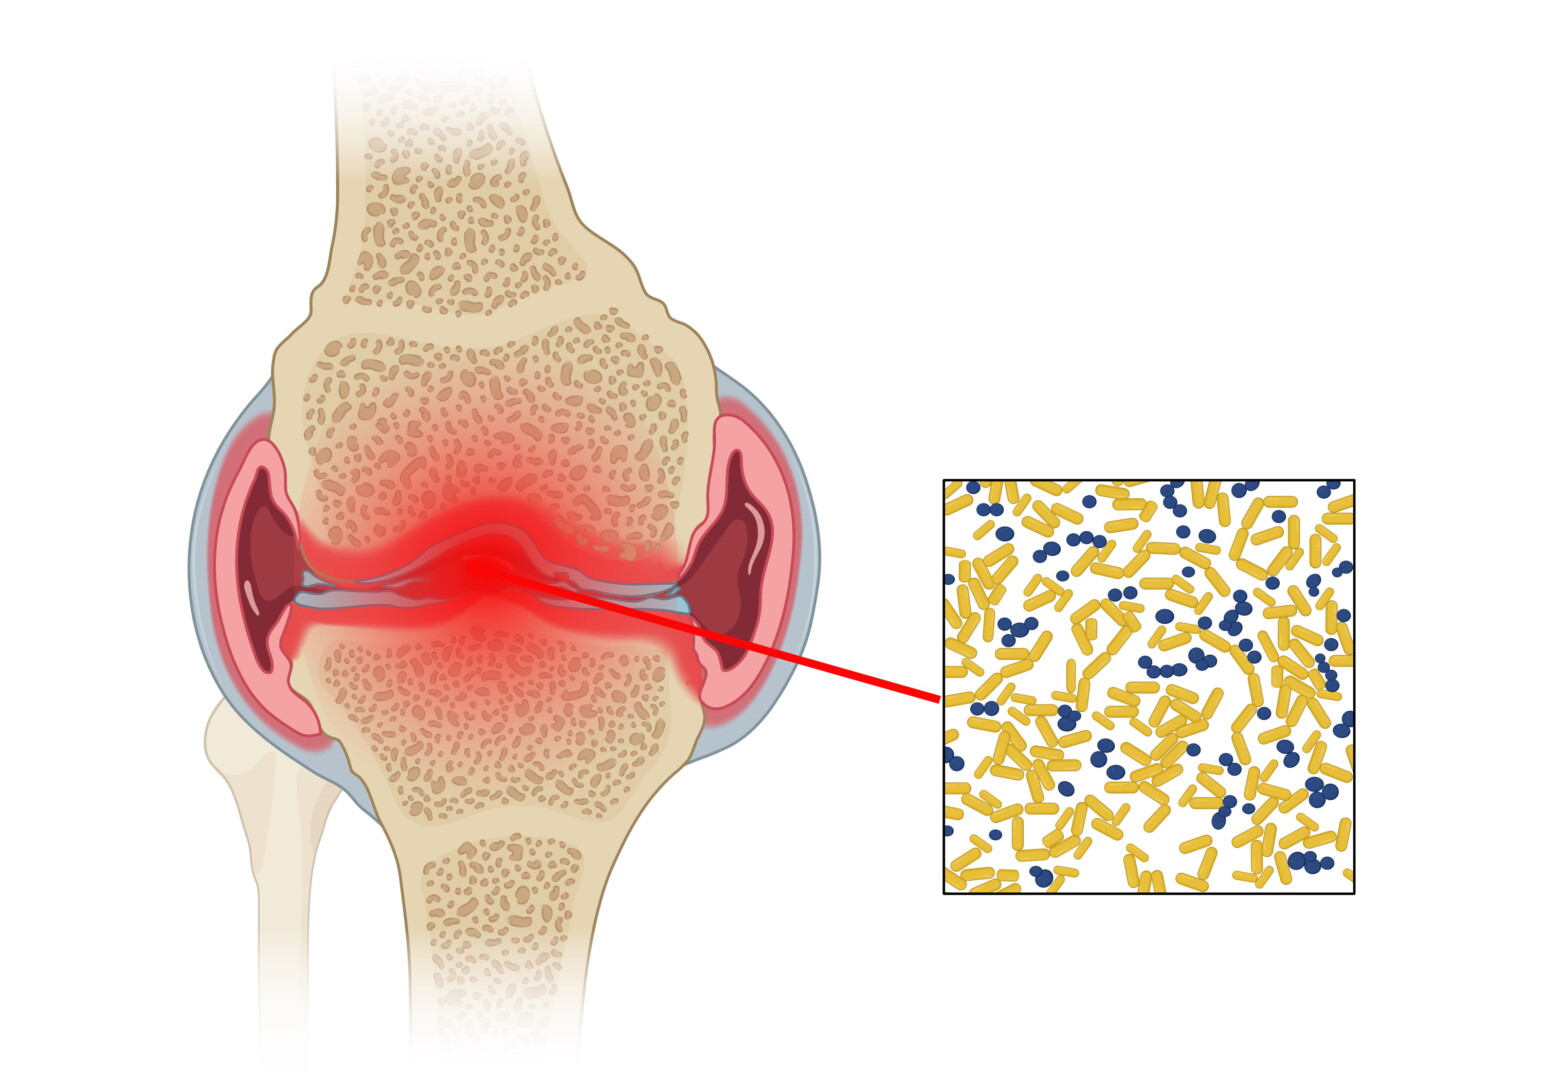

Dažniausiai ligą sukelia bakterijos, tačiau kartais septinis artritas išsivysto ir po kontakto su virusu arba grybeliu.

Visais atvejais infekcija išplinta į sąnarius ir sukelia uždegimą.

Iš visų septinio artrito kaltininkų – bakterijų, virusų, grybelių – dažniausiu sukėlėju nustatomas auksinis stafilokokas.

Šie patogeniniai mikroorganizmai, be kita ko, siejami su plaučių uždegimu, odos infekcijomis, sepsiu, kaulų ir sąnarių infekcijomis.